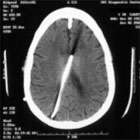

- "Slit ventricle" refers to the computed tomography (CT) or magnetic response imaging (MRI) finding of very small ("slit-like") ventricles.

- The finding of small ventricles in a shunted patient can be misinterpreted as a properly working shunt. Most patients with small ventricles (seen on CT or MRI) do not have the slit ventricle syndrome. Patients must be symptomatic.